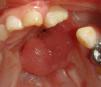

Se realiza una plantilla de aluminio con las dimensiones de la fístula, con la cual se diseña un colgajo ligeramente más grande. Se suturan los bordes laterales de la lengua a una platina acrílica en forma de herradura (fig. 2), que tiene como función estabilizar y dar soporte a la lengua para facilitar la toma del colgajo (figs. 3 y 4).